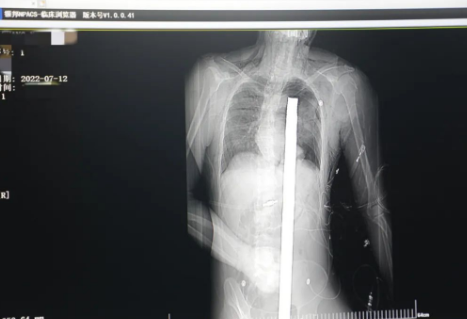

突發(fā)!太疼了,1.2米長的螺紋鋼從男子會陰部垂直穿入胸腔......7月12日下午16時(shí)10分,西安一處工地的一名26歲工友,不慎從10多米的高空墜落,不幸的是工地上一根直徑3厘米的螺紋鋼從男子會陰部垂直穿入體內(nèi),工地上的工友們小心翼翼地將連著的鋼筋截?cái)?。情況危急,立即送往西安國際醫(yī)學(xué)中心醫(yī)院急救中心,此時(shí)正是下午17時(shí)00分。

時(shí)間就是生命!此時(shí),西安國際醫(yī)學(xué)中心醫(yī)院展開了一場與生命賽跑的搶救,第一時(shí)間開辟綠色通道,急診X光片及CT顯示:異物經(jīng)會陰部貫穿盆腔、腹腔到達(dá)左側(cè)胸腔主動(dòng)脈弓水平。醫(yī)院創(chuàng)傷中心立即啟動(dòng)應(yīng)急預(yù)案,劉延彤副院長親臨指揮,下午17點(diǎn)48分,當(dāng)患者被送達(dá)手術(shù)室,胸外、心外、肝膽外科、胃腸外科,泌尿外科及麻醉科等多學(xué)科專家聯(lián)手對這名工友進(jìn)行“縱劈胸骨 前外側(cè)開胸探查 氣管及主支氣管修補(bǔ) 肺修補(bǔ) 血胸清除 開腹探查止血 腹膜后及盆腔探查......”手術(shù)。

情況緊急!術(shù)中探查后發(fā)現(xiàn),長120cm直徑3cm的螺紋鋼經(jīng)患者右側(cè)會陰部穿入,傷及直腸,途徑膀胱后方,左側(cè)髂總動(dòng)靜脈之間傷及左腎后,經(jīng)胰腺后方在肝脾之間穿破膈肌,在下肺靜脈前方穿入左肺穿破氣管及左右主支氣管膜部,止于主動(dòng)脈弓下水平,穿入體內(nèi)的部分達(dá)到75cm。